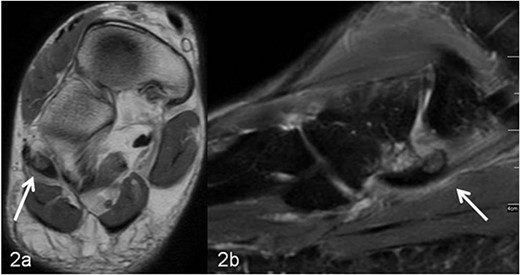

A 59-year-old man reported severe, load-dependent pain (7 out of 10 score points on the VAS) of his right foot, increasing over a period of about 1 month. He had no memory of having experienced trauma. Clinically, there was a pes planovalgus, a slight swelling, and warm sensation distolaterally of the malleolus lateralis over the course of the tendon of the peroneus longus muscle, where there was also clear pain upon pressure, and forced plantar flexion was very painful. For imaging diagnostics, conventional X-rays were taken, which revealed an elongated oval os peroneum with a size of 9.5 × 5 mm in a typical location (Fig. 1a and b). Furthermore, an MRI examination was performed, which revealed a clear perifocal soft tissue oedema of the os peroneum with involvement of the peroneus longus muscle, whereas a tendon rupture was ruled out (Fig. 2a and b).

(a, b) MRI imaging, (a) axial T1 weighted slice, the os peroneum is centrally located in the long peroneal tendon (marked with an arrow). In (b) sagittal T2 weighted fat-suppressed slice, around the os peroneum (marked with an arrow) and along the tendon there is a marked signal enhancement, corresponding to inflammatory fluid accumulation (tenosynovitis).

In addition to conventional X-rays, ultrasound and MRI are used for differential diagnosis and treatment planning. A dislocation, fracture, hypertrophic, or multisegmental form of the peroneal bone, with or without accompanying perifocal irritation and tenosynovitis or rupture of the long peroneal tendon, can be visualized effectively [7–13]. In our patient, an os peroneum of normal size and localization was found on conventional X-ray (Fig. 1a and b). In the MRI examination, there was clear perifocal soft tissue oedema with a tenosynovitis of the tendon of the peroneus longus muscle (Fig. 2a and b). At the same time, the arch of the foot was lowered and there was a marked pes planovalgus, so that, when everything was taken into consideration, it was assumed that our patient had subacute/chronic postural stress with accompanying perifocal inflammation.